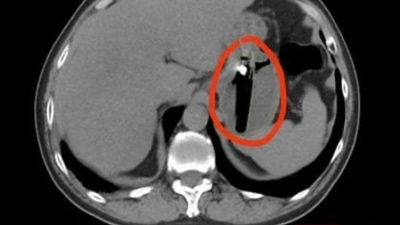

男子胃部隐痛反复一月竟是醉酒后误吞打火机 长达8厘米异物潜伏